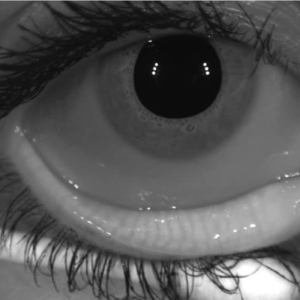

Healthy Meibomian Glands vs Gland Loss

As gland structure changes over time, the eye becomes less able to maintain a stable tear film. Early treatment focuses on preserving gland function and improving how the remaining glands work.